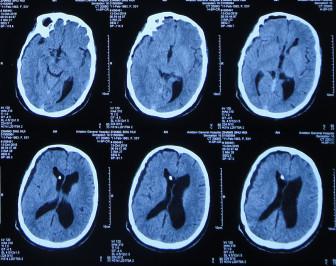

当天头颅CT:脑积水右侧侧脑室分流术后,脑室扩张并间质性脑水肿(图-12)。

图-12:2016年10月7日头颅CT

住院第2天即2016年10月8日,进行了原侧脑室脑脊液分流管去除术+右侧侧脑室外引流术,术后当天复查头颅CT:脑室引流术后状态(图-13)。

图-13:2016年10月8日头颅CT

引流术后第5天即2016年10月13日,复查头颅CT:右侧脑室较入院时缩小(图-16)

图-16:2016年10月13日头颅CT

第2次术后40天即2016年12月3日,头颅CT:脑室较入院时明显缩小(图-20)。

图-20:CT 对比图